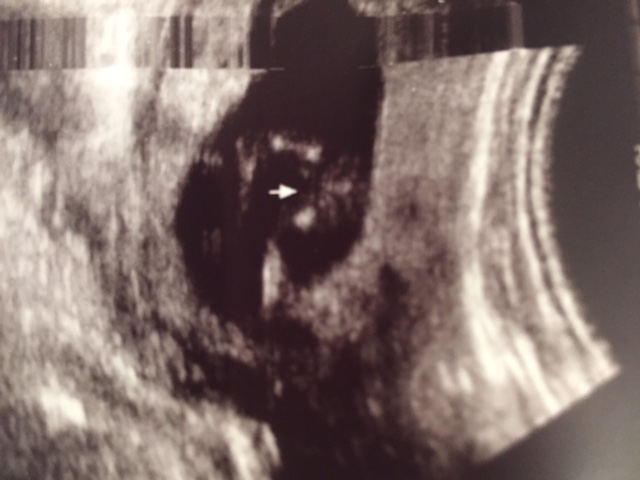

Ok so I had my 13 weeks ultrasound today and the technician said she was 99.9% it is a... I won't tell just yet because I would love to hear your opinion. I'm so happy that I can't believe this is actually happening and I'm afraid that my 20 week scan will show something different!!! Here are the pictures:

Attachment 24292